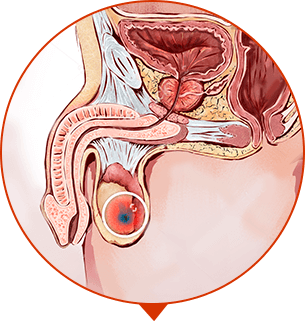

CONTROLLATI! SINTOMI DELLA PROSTATITE:

Una volta all’anno o una volta ogni sei mesi sentite tirare nella zona del pube

Ogni tanto sentite delle lievi pressioni locali

Vi siete accorti che andate in bagno più spesso

Un testicolo sembra pendere più dell’altro

Avete a volte problemi di diarrea e affini

Vi sembra che la vostra erezione sia più debole

Si è abbassata la libido

Avete avuto almeno una volta difficoltà ad orinare

SE AVETE TROVATO PER LO MENO UNO DI QUESTI SINTOMI, DOVETE INIZIARE LA CURA AL PIU’ PRESTO!

Il dolore vi disturba. La prostatite non permette una vita normale. Starete ancora peggio entro 1-2 anni. Sterilità. Sangue durante orinazione ed eiaculazione. Calcoli renali (fino a 500 ml). Infiammazioni interne.